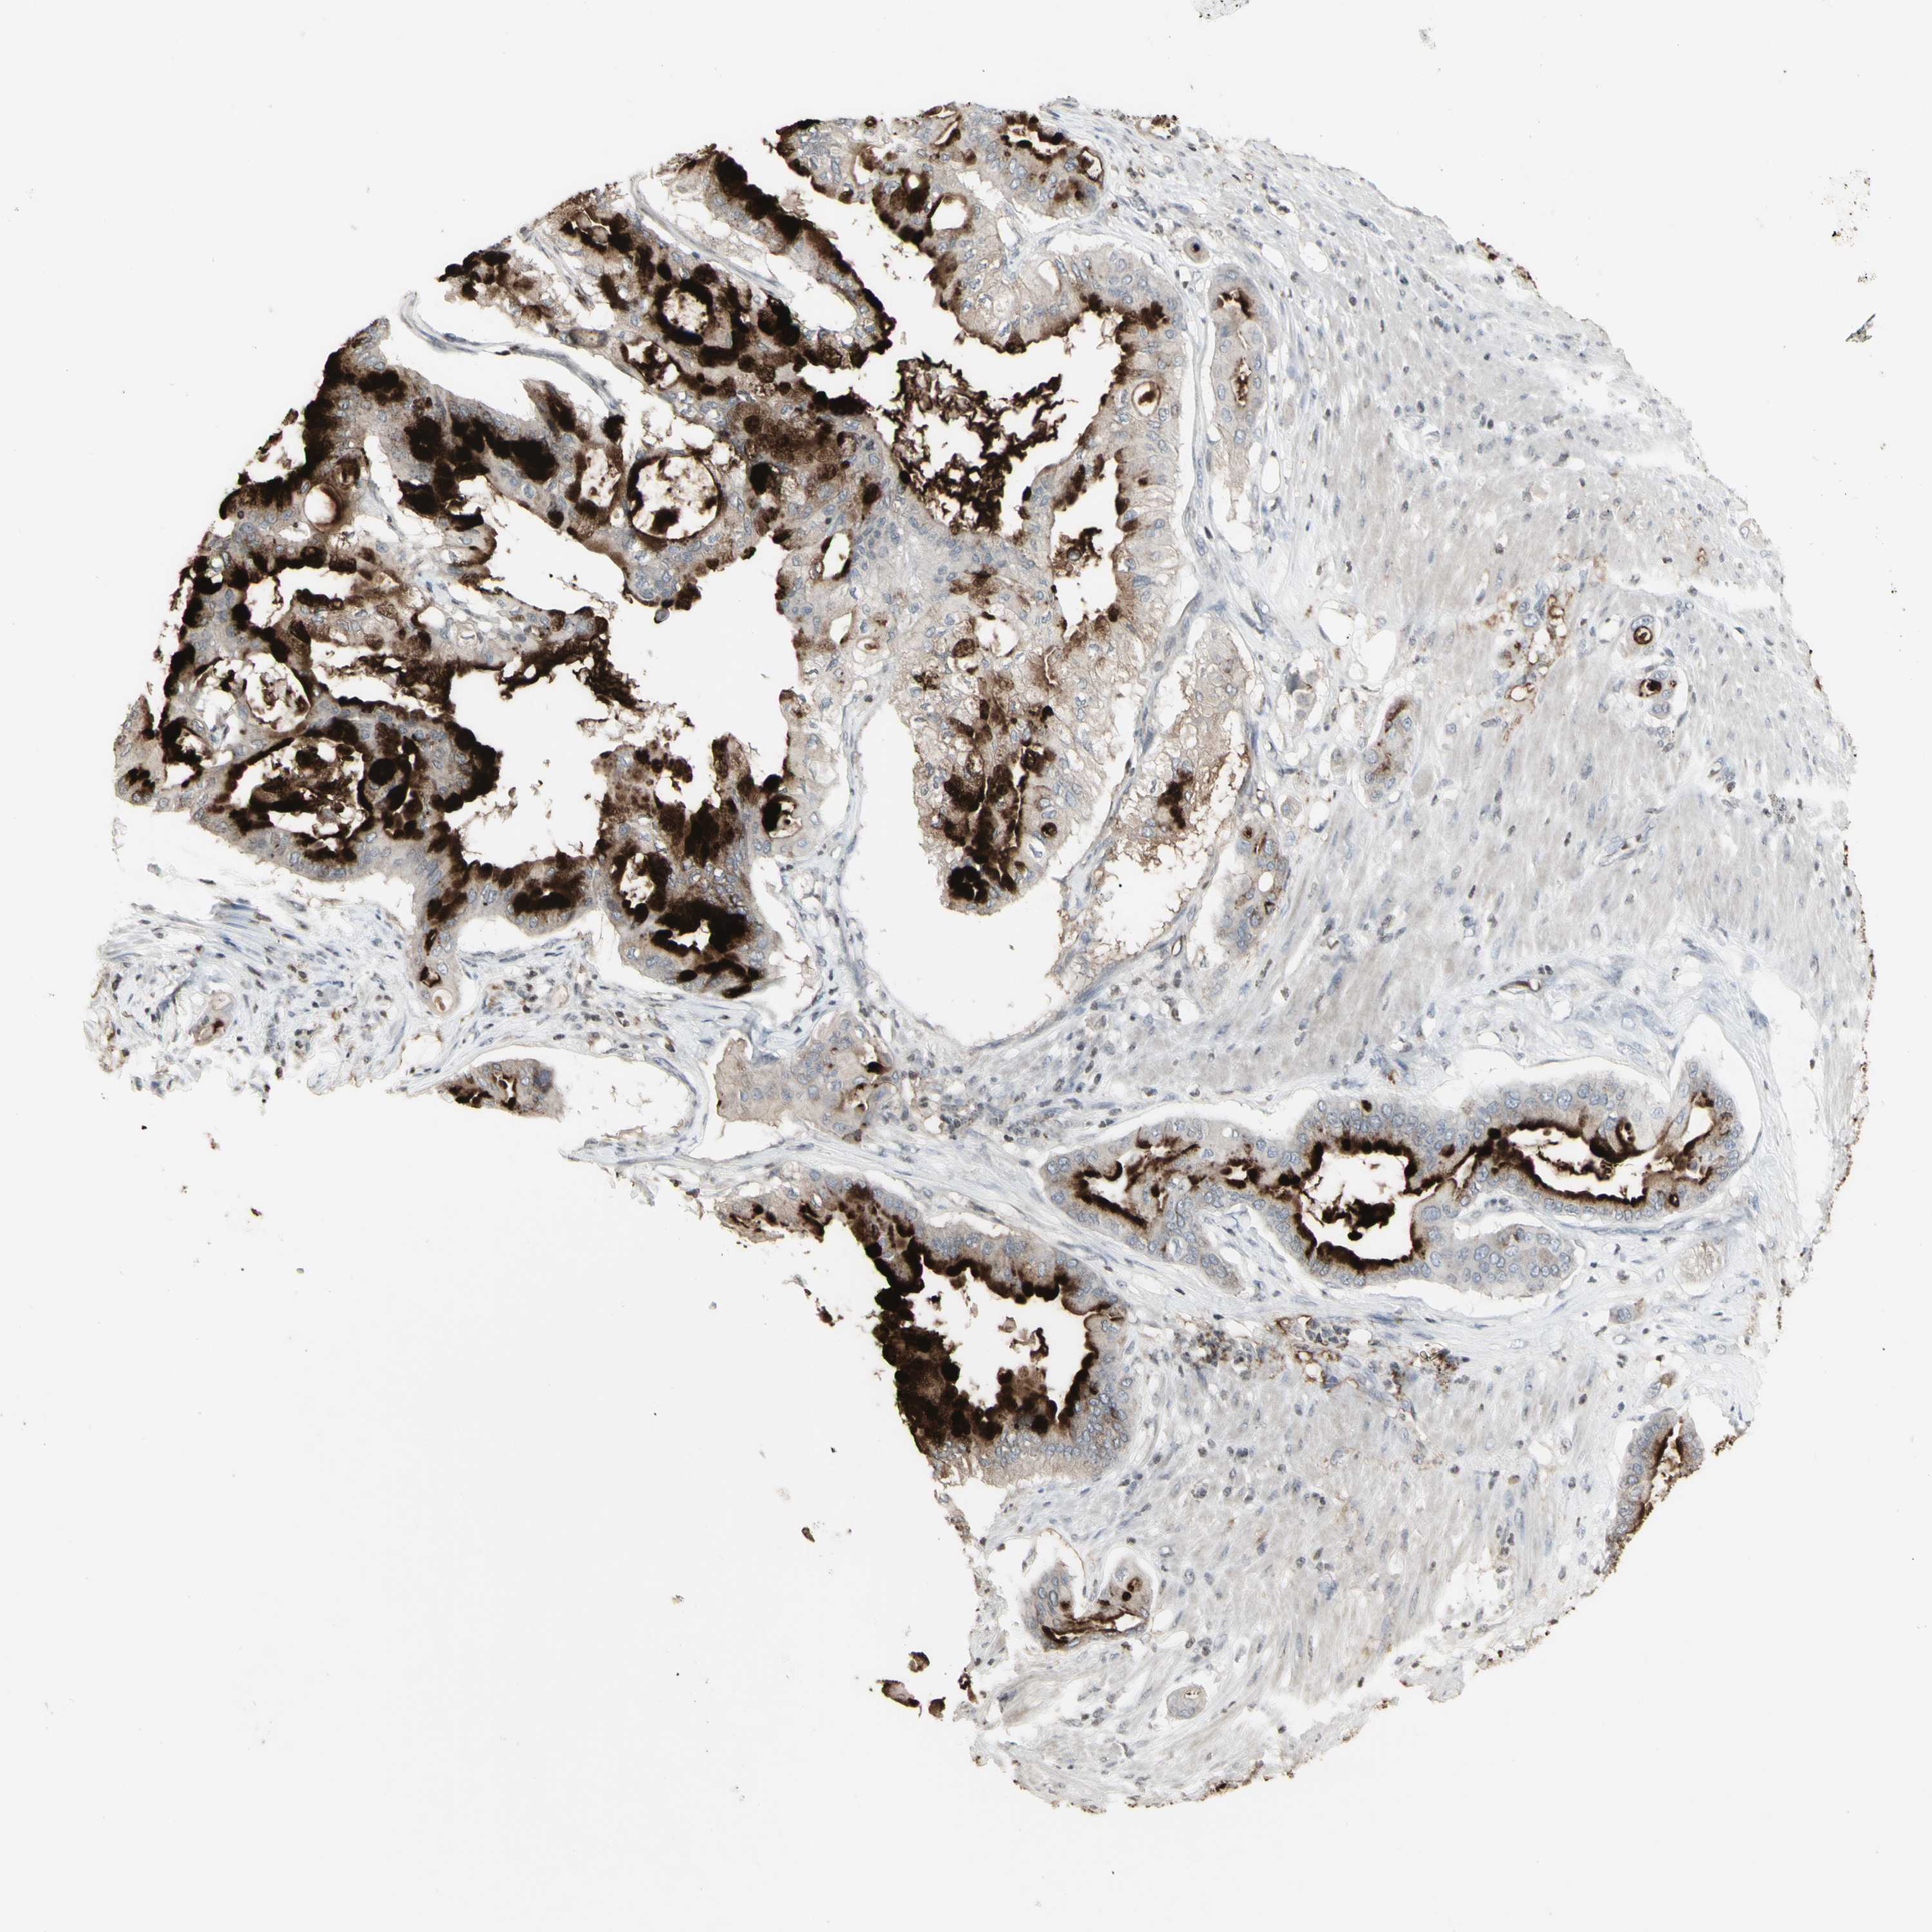

PANCREATIC CANCER - Protein expressioni

A mouse-over function shows sample information and annotation data. Click on an image to view it in a full screen mode. Samples can be filtered based on level of antibody staining by selecting one or several of the following categories: high, medium, low and not detected. The assay and annotation is described here.

Note that samples used for immunohistochemistry by the Human Protein Atlas do not correspond to samples in the TCGA dataset.

Antibody stainingi

Antibody staining in the annotated cell types in the current human tissue is reported as not detected, low, medium, or high, based on conventional immunohistochemistry profiling in selected tissues. This score is based on the combination of the staining intensity and fraction of stained cells.

Each image is clickable and will lead to virtual microscopy that enables deeper exploration of all samples and also displays staining intensity scores, fraction scores and subcellular localization as well as patient and tissue information for each sample.

Adenocarcinoma, NOS

Adenocarcinoma, metastatic, NOS